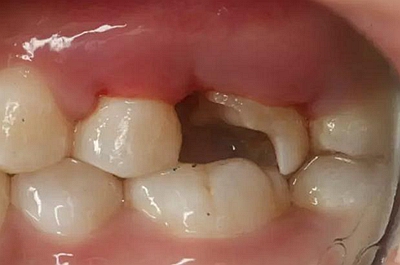

病例一 女性,20歲,大學生,要求補牙,檢查口內(nèi)可見A6大面積缺損,近中牙齦息肉,拍X片,根管充填物略差,但根周未見明顯陰影,口內(nèi)檢查無叩痛。建議患者冠延長手術+高嵌體修復。

患牙遠中邊緣嵴完整,強度沒有降低,故擬保留遠中邊緣嵴,高嵌體修復。首先去除腐質(zhì)及原墊底材料,流體樹脂+3M Z350XT樹脂墊底。局麻下行冠延長手術。在此需要提及個人的一個觀點。冠延長手術原則上要求3-6個月以上才能永久修復。但是個人喜歡后牙肩臺建立在齦上,所以修復后的修復體邊緣位于牙齦上方1mm,對牙周的愈合影響較?。ㄈ绻麨辇l下邊緣則要慎重),故該患者術中按照齦上邊緣的設計進行冠延長手術。以下為術中: